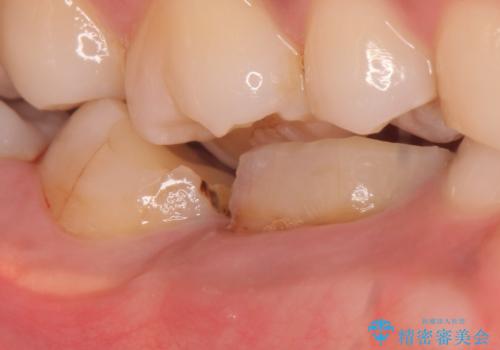

- 奥歯が欠けてしまったので診て欲しいといらっしゃった方の症例です。

再根管治療終了後、オールセラミッククラウンによる補綴を行いました。

今回用いたオールセラミッククラウンはジルコニアフレームという白い素材の上にセラミックを盛っているため、審美性が非常に高いのが特徴です。